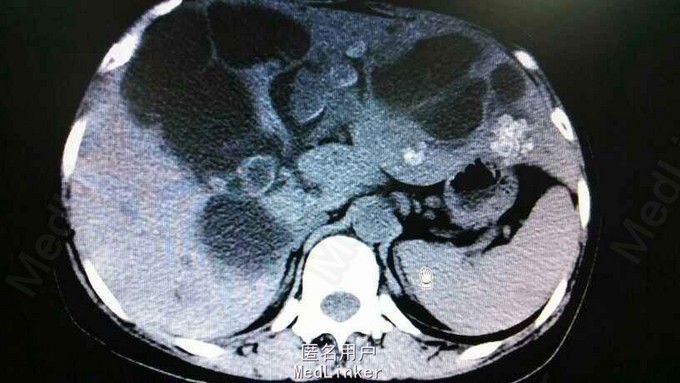

查体:右上腹轻压痛,无反跳痛,余无特殊。辅助检查,肝功,血象正常。腹部CT示肝内多发结石伴胆管囊状扩张。胆总管结石。见图